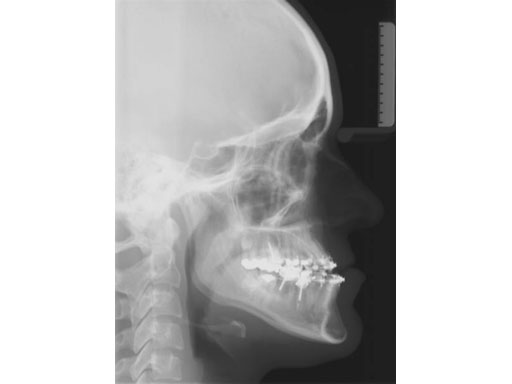

Lefort I maxillary osteotomy, bilateral sagittal osteotomies, and a genioplasty, all fixed with matrix orthognathic system used in a 19-year-old female with significant skeletofacial deformity including maxillary hypoplasia, mandibular excess, and laterognathia.

Fig 2a-c Postoperative images.